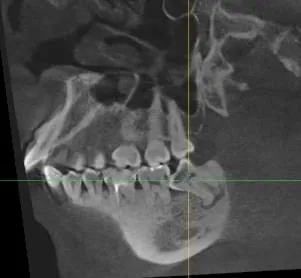

Пациент с жалобами на боли в зубе 4.8, в связи с обострением хронического периодонтита частично ретинированного дистопированного зуба 4.8.

Проведено удаление зуба мудрости, рана промыта растворами антисептиков, рана ушита.